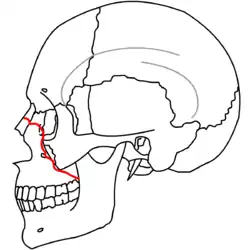

|

| Le Fort II fractures | |

At the beginning of the 20th century, René Le Fort mapped typical locations for facial fractures; these are now known as Le Fort I, II, and III fractures (right).[7] Le Fort I fractures, also called Guérin or horizontal maxillary fractures,[14] involve the maxilla, separating it from the palate.[15] Le Fort II fractures, also called pyramidal fractures of the maxilla,[16] cross the nasal bones and the orbital rim.[15] Le Fort III fractures, also called craniofacial disjunction and transverse facial fractures,[17] cross the front of the maxilla and involve the lacrimal bone, the lamina papyracea, and the orbital floor, and often involve the ethmoid bone,[15] are the most serious.[18] Le Fort fractures, which account for 10–20% of facial fractures, are often associated with other serious injuries.[15] Le Fort made his classifications based on work with cadaver skulls, and the classification system has been criticized as imprecise and simplistic since most midface fractures involve a combination of Le Fort fractures.[15] Although most facial fractures do not follow the patterns described by Le Fort precisely, the system is still used to categorize injuries.[5]